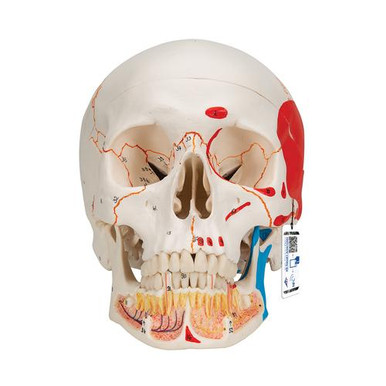

mqdefault.jpg, 3B Scientific Classic Painted Human Skull Anatomy Model (3

3B Scientific Classic Painted Human Skull Anatomy Model (3I22-044 骨学実習の手びき 寺田春水 藤田恒夫 著 南山堂